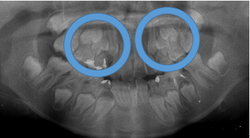

初診時

治療1年6カ月後

このように、1年6ヶ月間、通院して頂ければ治療計画どうりの目標は達成されます。

しかし、上下の顎骨の状態が改善されたからと言って永久歯が綺麗に並ぶわけではありません。

○印の中にある突起は永久歯の犬歯です。

但し、本来顎骨が劣成長であった場合はその中にある永久歯は著しい位置異常を起こしている場合が多い為に上下顎骨の大きさや咬み合わせの高さが改善したとしても、歯並びが悪くなる事がほとんどです。

その場合は永久歯の歯列矯正の計画の契約を結び永久歯の綺麗な歯並びと咬み合わせに改善していきます。